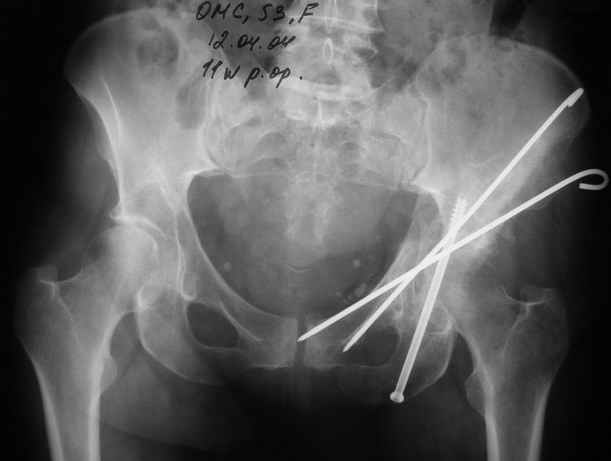

Anatoly F Lazarev 03 Сентябрь 2004, 22:18

Женя! Класный перелом. Отлично репонируется изнутри таза, но лучше фиксированть сзади. Классический перелом для двустороннего доступа.

Однако есть альтернатива. Репозиция из подвздошного доступа тазовыми щипцами с разнодлинными браншами или тазовым пистолетом, а фиксация задней колонны через седалищный бугор или тазрвыми винтами 4,5 или каннюлированными 6,5 или 7,3. По-моему я посылал на ортофорум такой снимок, когда жаловался на ишемический неврит седалищного нерва через сутки после операции. Не забудь про шейку бедра - мне кажется будет хорош длинный PFN любой фирмы, какую ты найдешь, а нет так UFN + miss a nail, как это здорово делают мои земляки - Ебурбуки. Пока.

27.01.04

02.02.04

10.02.04

12.04.04

02.06.04

Высылаю пример еще одного случая, остеосинтез пластиной из подвздошного доступа.